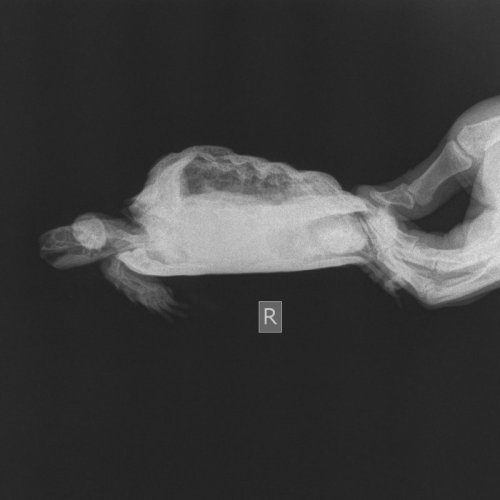

strawberrymilk Ваше имя: Дарья Локация: Пенза Опубликовано: 2 октября 2020 Автор Опубликовано: 2 октября 2020 @moth Съездили в вет. клинику на рентген. Ветеринар сказал, что у неё есть лёгочная недостаточность из-з продавленных 2 пластин. Вес черепах: 0.56, 0.48 и 0.42 кг.

Консультанты moth Ваше имя: Мария Локация: Москва Опубликовано: 2 октября 2020 Консультанты Опубликовано: 2 октября 2020 @victoria146 в Воронеже есть герпетолог Татьяна Волкова https://vk.com/vetpomoshvrn. Я не знаю на сколько она квалифицированный врач, но по постам в ВК я не нашла ничего плохого или сильно неправильного от неё. Думаю рентген она точно сможет сделать. Но вообще рентген с контрастом делают только при подозрении на непроходимость. Всё остальное можно посмотреть просто так, главное в правильной проекции и чтобы оборудование было хорошее. @strawberrymilk по снимкам врач увидел фолликулы увеличенные, они давят на другие органы. Нужно колоть кальций, Элеовит, делать вибротерапию. У самки какой вес?